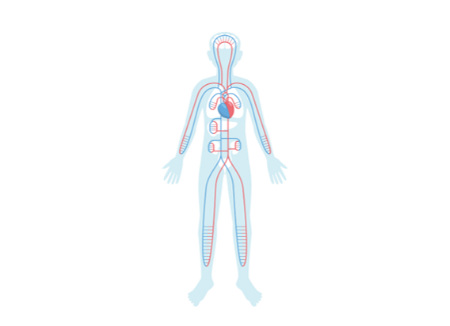

歯周病と全身疾患の関係

歯周病は全身疾患を引き起こすリスクを高めます。歯ぐきの毛細血管などから体内に侵入し、強い毒素を放出しながら全身を巡ります。結果的に、動脈硬化に伴う心筋梗塞などの心臓病、糖尿病の発症や進行の原因にもなりえます。また、妊娠中の場合は子宮の収縮を強めて早産や低体重児出産のリスクを高めると言われています。